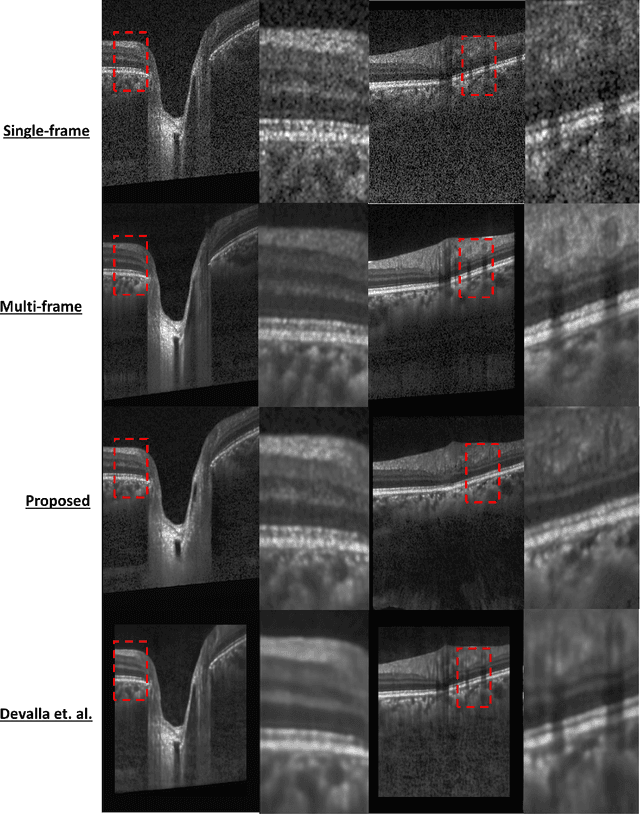

Abstract:Speckle noise and retinal shadows within OCT B-scans occlude important edges, fine textures and deep tissues, preventing accurate and robust diagnosis by algorithms and clinicians. We developed a single process that successfully removed both noise and retinal shadows from unseen single-frame B-scans within 10.4ms. Mean average gradient magnitude (AGM) for the proposed algorithm was 57.2% higher than current state-of-the-art, while mean peak signal to noise ratio (PSNR), contrast to noise ratio (CNR), and structural similarity index metric (SSIM) increased by 11.1%, 154% and 187% respectively compared to single-frame B-scans. Mean intralayer contrast (ILC) improvement for the retinal nerve fiber layer (RNFL), photoreceptor layer (PR) and retinal pigment epithelium (RPE) layers decreased from 0.362 \pm 0.133 to 0.142 \pm 0.102, 0.449 \pm 0.116 to 0.0904 \pm 0.0769, 0.381 \pm 0.100 to 0.0590 \pm 0.0451 respectively. The proposed algorithm reduces the necessity for long image acquisition times, minimizes expensive hardware requirements and reduces motion artifacts in OCT images.